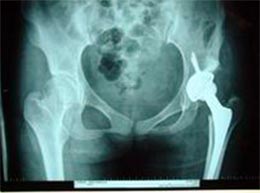

病例四

患者女性,34岁,左髋关节先天性脱位,股骨头坏死,疼痛明显,活动受限。采用生物固定全髋关节置换术,

髋臼予以加深后,用切除的自体股骨头植骨,髋臼稳定好。术后3年复查,假体没有松动,关节功能良好,没有疼痛。